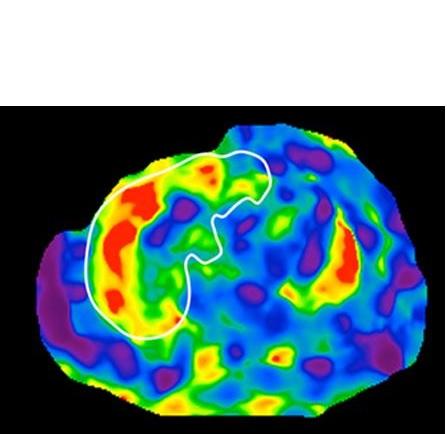

- le test permet même de différencier l’existence d’un parent au premier degré atteint, d’une cirrhose non diagnostiquée avec une précision de 87% ; ces résultats sont ici confirmés par imagerie par résonance magnétique (IRM : voir visuel ci-contre de scanner du foie avec cirrhose).